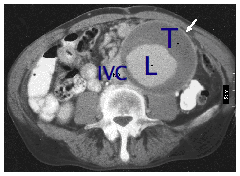

Unfortunately, many people will not know if they have an aortic aneurysm, because they rarely cause symptoms until they burst. Aortic aneurysms are sometimes found during a routine examination for other conditions such as prostate problems or gallstones. If you are a man over the age of 60 years, a smoker with high blood pressure and have a brother or father with an aortic aneurysm, then this puts you at increased risk. If you also have hardening of the arteries at other sites (eg previous stroke or heart attack) then you may also be at increased risk. Occasionally patients present with embolism of blood clot in the aneurysm sac to the lower limb arteries. This occurs when clot is dislodged and travels down to the arteries to the legs and interferes with the blood supply causing scattered areas of mottling in the feet and sometimes gangrene. Although examination by your doctor may be helpful in diagnosing a large aortic aneurysm, it is not a sensitive method of diagnosing smaller aneurysms. The best way to diagnose an aneurysm is with an ultrasound scan of the abdomen. This is a very quick, simple, accurate and safe test that is also commonly used to examine babies in the womb. Occasionally, patients experience abdominal and back pain and the aneurysm becomes tender before it ruptures. If this happens and you know you have an aneurysm, then it is important to seek emergency medical advice. Before surgery most patients will undergo CT (computed tomography) scanning to show the aneurysm in more detail. The picture below is a CT scan of an aneurysm. This picture represents a slice across the abdomen. The spinal column and back is shown in the lower portion of the picture.

White arrow points to aneurysm

T is thrombus or blood clot inside the enlarged artery

L is the lumen or part of the artery where blood is flowing.

IVC is inferior vena cava or the main vein in the abdomen.